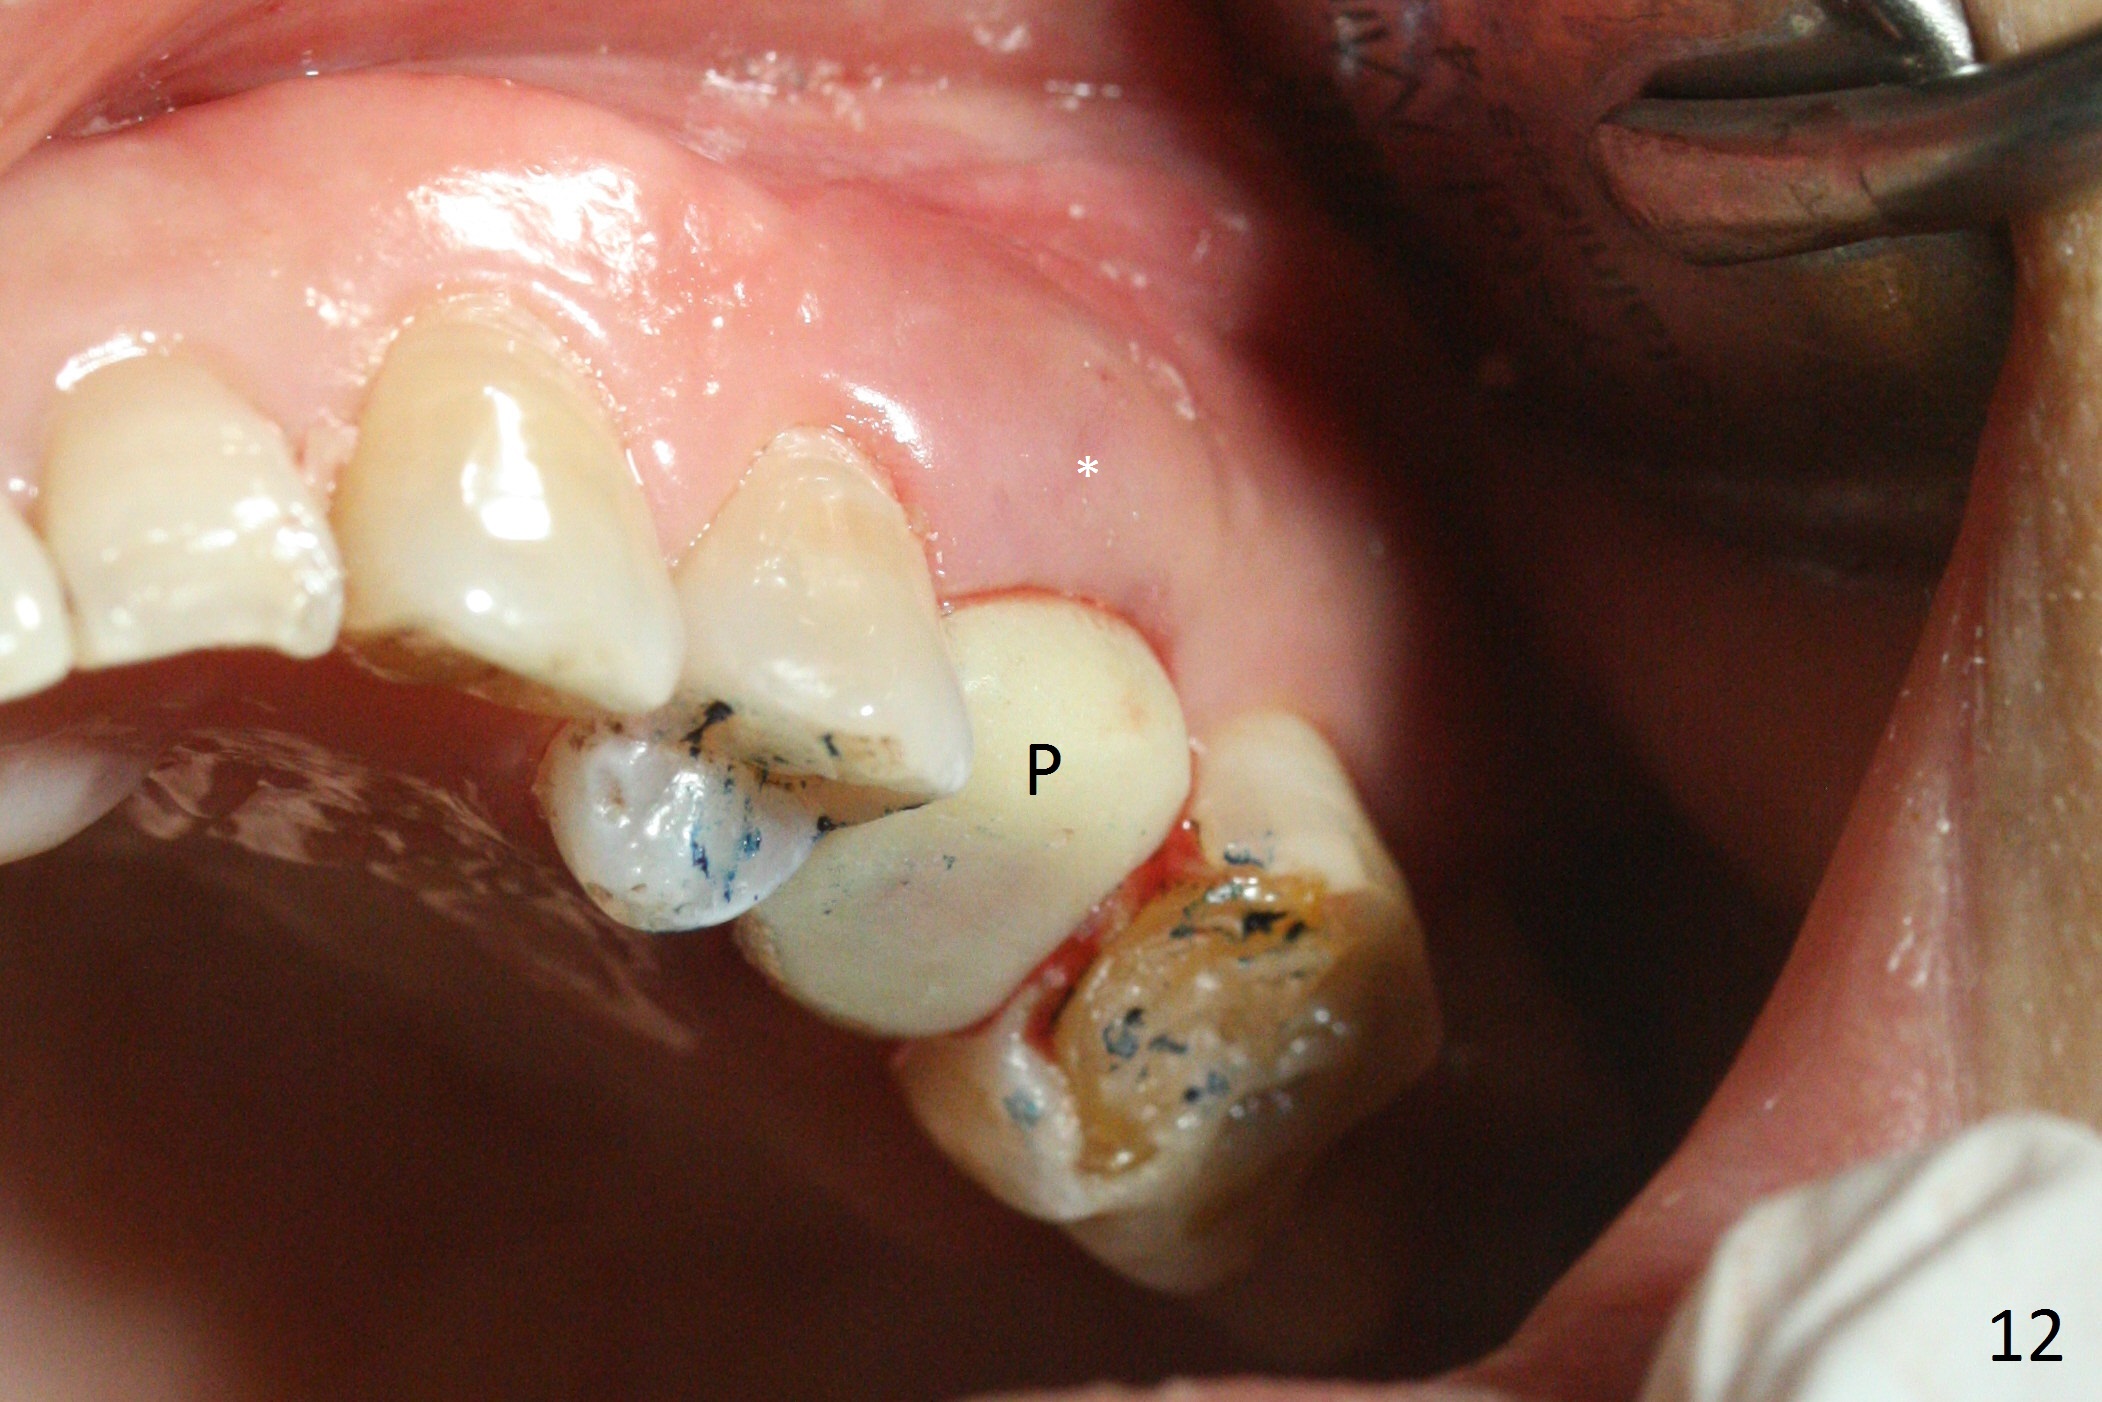

The buccal gingiva over the tooth #13 (Fig.1 white *) with crack (Fig.2 (mesial view of the extracted tooth)) is erythematous with deep buccal (B) pockets, which do not appear to extend the level of exostosis of the neighboring teeth (Fig.1 black *), i.e., coronal to the apical end of the crack with granulation tissue (Fig.2 *). Osteotomy is initiated with a 1.6 mm drill in the palatal aspect of the socket (Fig.3) so that an implant will be placed palatal (Fig.8,11) and there is enough buccal gap for bone graft (Fig.8 *). After withdrawal of 3.3 mm Magic Drill (trephine bur), the osteotomy (Fig.4 O) plug (red outline) is intentionally left in situ. When a 4x11 mm dummy implant is placed (Fig.5 (green outline), 6), the plug is compressed (Fig.5). With placement of a definitive implant (4.5x13 mm, Fig.7 (green), 9), the plug as well as the sinus floor (Fig.4 SF) is lifted (Fig.7 red curved line), 9 (arrowheads)). In brief the autogenous bone is used for sinus lift. There is no intra- or post-op nasal hemorrhage. With a small piece of gauze (Fig.8 G) in the implant well, allograft is placed in the buccal (mainly) and palatal gaps until the level of the implant plateau. Then a 4.5x4(3) mm abutment is placed (Fig.9-10 A). Next another piece of gauze is placed in the space corresponding to the abutment cuff (Fig.11 G) for fabrication of an immediate provisional (Fig.12 P). More bone graft is placed in the soft tissue zone (dual zone technique) after gauze removal and before provisional seating. With dual zone bone graft technique and provisional support, the soft tissue atrophy should be expected to be minimal (Fig.12 *). The zone of exostosis (more coronal) should be much less, since the bone density in the zone is high.

The buccal gingival inflammation subsides 1 week postop (Fig.13,14). There is no bone loss 4 months postop (Fig.15,16). The crown is recemented 6 months post cementation (probably due to short abutment); there is a residual cement (Fig.17 <), which is removed (Fig.18).